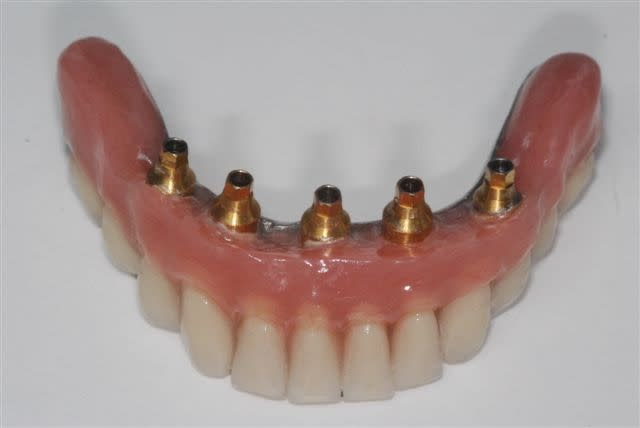

j'avais promis de montrer la suite et la fin du cas.

Alors voilà: empreinte pick-up mixte (silicone et plâtre snowhite), RIM avec cire calée sur des piliers hauts, et aujourd'hui retrait des implants provisoire et vissage de la prothèse.

il se trouve que la parallélisme des implants était tel que j'ai pu me passer des piliers multi. L'empreinte au plâtre est sortie sans forcer et l'insertion ce matin à la pose s'est faite de même (je pensais à l'extrême limite devoir shorter un peu les bords des hexagones, mais même pas), juste au dessus des hexagones on a une liaison conique à 11°. Une prothèse est déjà réalisée tout en résine et incluant les piliers usinés, puis la résine est évidée en lingual, une maquette en cire est réalisée en épousant le plus possible les piliers. Elles est ensuite coulée, adaptée contre les piliers et enfin soudée au laser avec apport de cobalt conte les piliers....la passivité est conservée. Maintenant, c'est la première fois que je n'utilise pas les piliers multi, ici c'est assez par hasard que les implants aient été parallèles. c'est vrai que le coût en a été moindre mais ce n'était pas l'objectif premier.

j'attends au moins 2-3 mois, mais avec ce type de connectique (conique à 11°, serrage 25 N.cm) je n'ai pas constaté de necessité à resserer après quelques semaines.

une vue de l'armature lors de la finition au labo